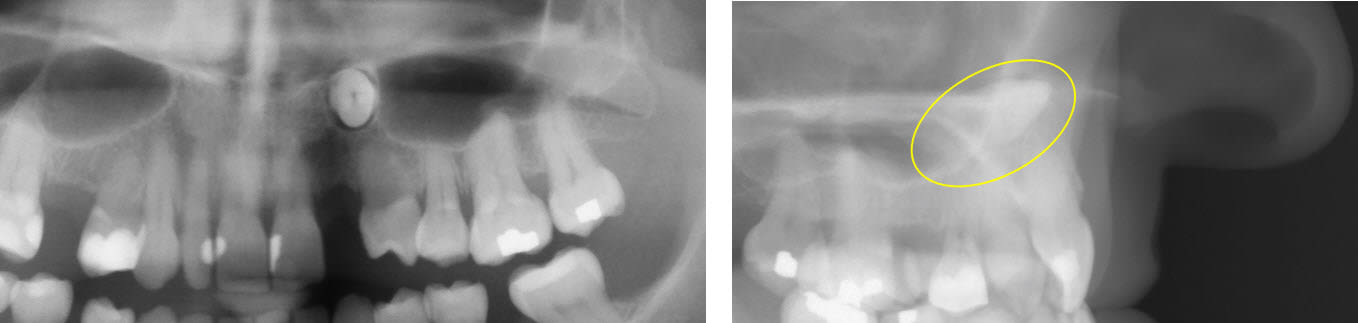

Exemple de traction discrète de canines chez une adulte. Système CT8.

j avoue que vu l axe à presque 90 degré de la canine je n ai même pas pensé à la solution ortho .

Sur le deuxième cas présenté (celui des radios) le parodonte n'a pas suivi la 23, créant des poches infraosseuses qui vont être compliquées à gérer, et risque de compromettre l'avenir de cette canine. On a même l'impression que la 24 en a pris un coup, "parodontalement" parlant, et le contexte d'édentation partielle préexistant ne va pas aider sur le plan occlusal...

Je suppose qu'il y a eu une traitement paro-occluso-prothèse derrière pour pérenniser et stabiliser le tout. Sinon était-ce la bonne indication ?

Tu as raison, ce n'était pas un traitement à présenter sur ce forum. J'ai supprimé les images des radios. Toutes les fois où j'ai présenté ce cas en conférence ou en cours, je l'ai fait sous forme d'animation PP et disais en substence que s'il n'y avait pas beaucoup d'os à l'arrivée, il y en avait encore moins au départ. À partir du moment où on considére (bouboule) qu'il y a quand même assez d'os au départ (!) pour placer un implant, le problème se pose différemment et l'indication de la traction ne se pose évidemment plus.